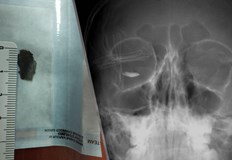

Метално чуждо тяло с размер 15 мм проникна в окото

...... отдаденост на професията и голям опит", коментира проф. Александър Оскар, ръководител на Катедра по офталмология и началник на Клиника по очни болести към УМБАЛ "Александровска".

Част от пирон забит в склерата е причината млад мъж

...... му всяка една такава травма крие потенциален риск за увреда и на здравото око дори години след нея и е важно хората да знаят това.